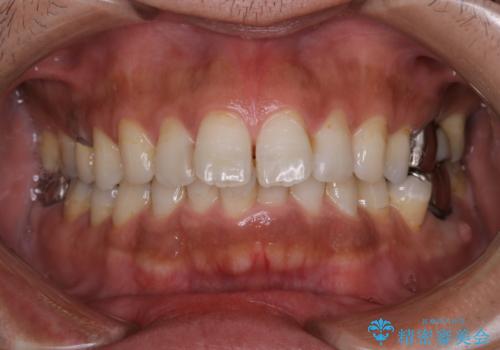

タバコやコーヒーによる着色落とし(PMTC)

- 着色を落としてほしいとのことで来院されました。

PMTC60分コースを行いました。

半年に一度クリーニングしているとのことでした。タバコとコーヒーの着色でした。

着色に厚みがあるため、エアーフローも使用して除去しました。